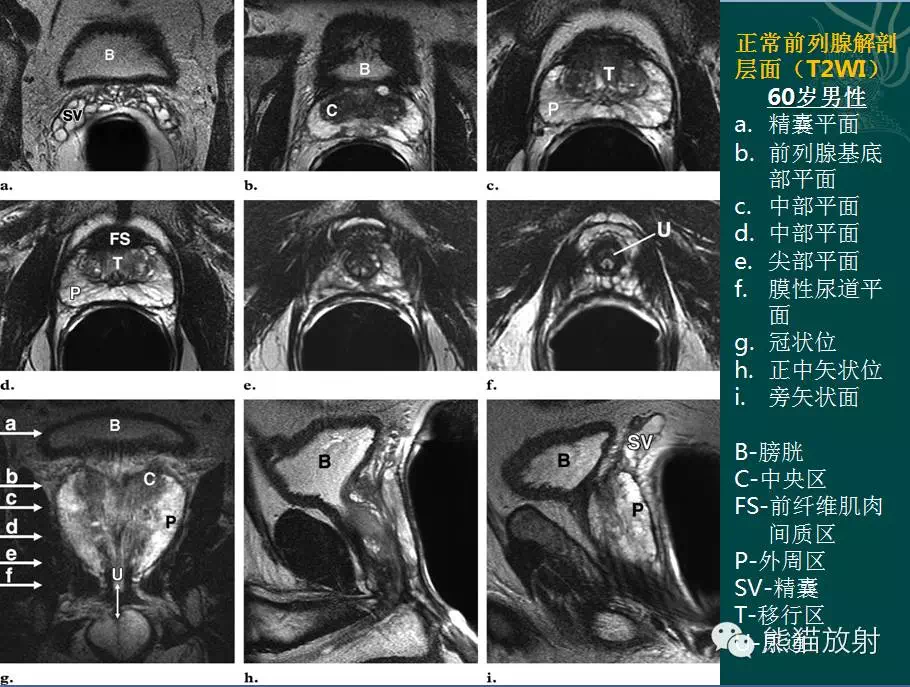

前列腺癌为临床常见疾病,需掌握其影像学表现!本期主要内容:前列腺解剖(分区)、MR扫描技术(平扫、DWI、DCE)、正常前列腺MRI表现、前列腺癌的MRI表现(分期、肿瘤突破包膜及侵犯精囊的诊断要点、DWI表现、动态增强表现)